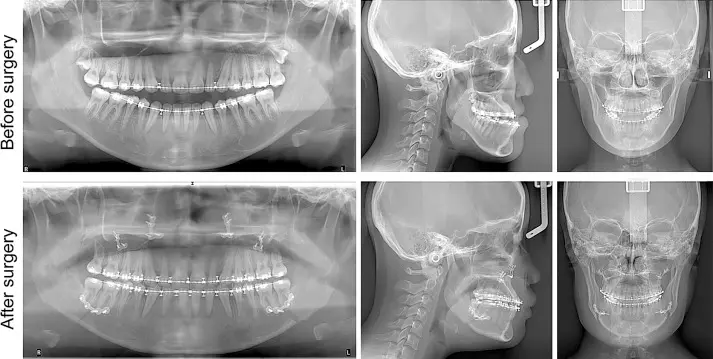

برخی از ناهنجاریهای فکی و دندانی تنها با ارتودنسی قابل اصلاح نیستند و نیاز به ترکیب آن با جراحی فک دارند. این روش که به ارتوسرجری معروف است، برای بیمارانی که مشکلات شدیدی در موقعیت فکها دارند، توصیه میشود. ارتودنسی قبل از جراحی، دندانها را در موقعیت مناسب قرار میدهد و پس از جراحی، تنظیمات نهایی انجام میشود تا فک و دندانها هماهنگ شوند.

۱. معاینه و تشخیص: متخصص ارتودنسی مشکلات فکی بیمار را ارزیابی کرده و برنامه درمانی مناسب را تعیین میکند.

۲. ارتودنسی پیش از جراحی: دندانها با براکتهای ثابت مرتب میشوند تا برای جراحی آماده شوند.

3. جراحی فک: جراح فک و صورت موقعیت استخوان فک را اصلاح میکند تا هماهنگی بهتری ایجاد شود.

4. ارتودنسی بعد از جراحی: برای تکمیل درمان و تثبیت نتایج، تنظیمات نهایی دندانها انجام میشود.